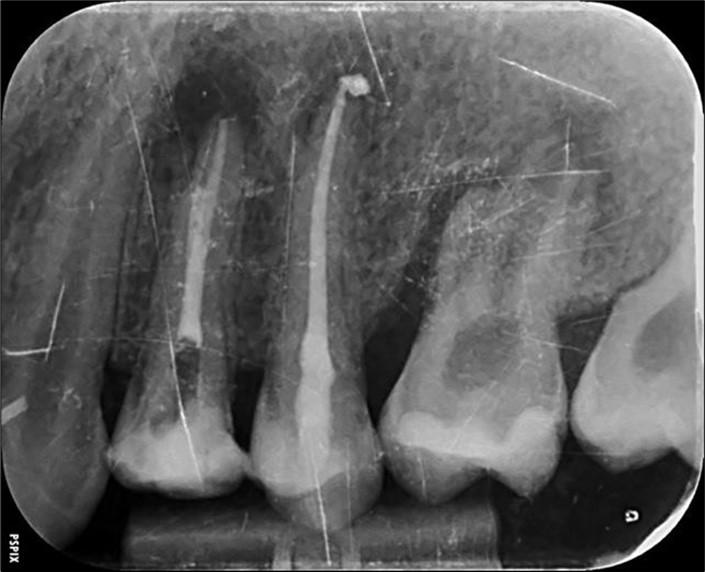

Periapical radiography (phosphorus number 2 plaque and X-MIND® Unity; Acteon) and cone-beam computed tomography (X-MIND® 3D; Acteon) (80 × 80, 150 Micron) were performed and showed periapical lesions on teeth 14, 15, 16, 24, 25, 26, 35, 36, and 46, as well as advanced endo-perio lesions on teeth 26 and 16. orthopantomogram (X-MIND® 3D; Acteon) and bitewings (phosphorus number 2 plaque and X-MIND® Unity; Acteon) also showed wide pulp chambers and roots canals. Figure 1, Figure 2

Figure 2.2. 3, 4, and 5 show periapical lesions on teeth 15, 16, 24, 25, 26, 35, 36, and 46.

2. 3, 4, and 5 show periapical lesions on teeth 15, 16, 24, 25, 26, 35, 36, and 46.